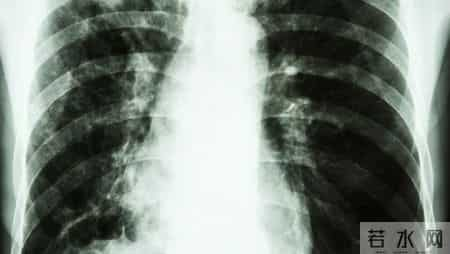

第四,肺功能检查结果不能脱离症状、影像、病史来看。

有些患者FEV1下降明显,却几乎无症状;也有些人症状重,但肺功能尚可。这正是慢阻肺的“个体差异性”体现。医生会综合HRCT影像、血气分析、咳痰情况做综合判断。